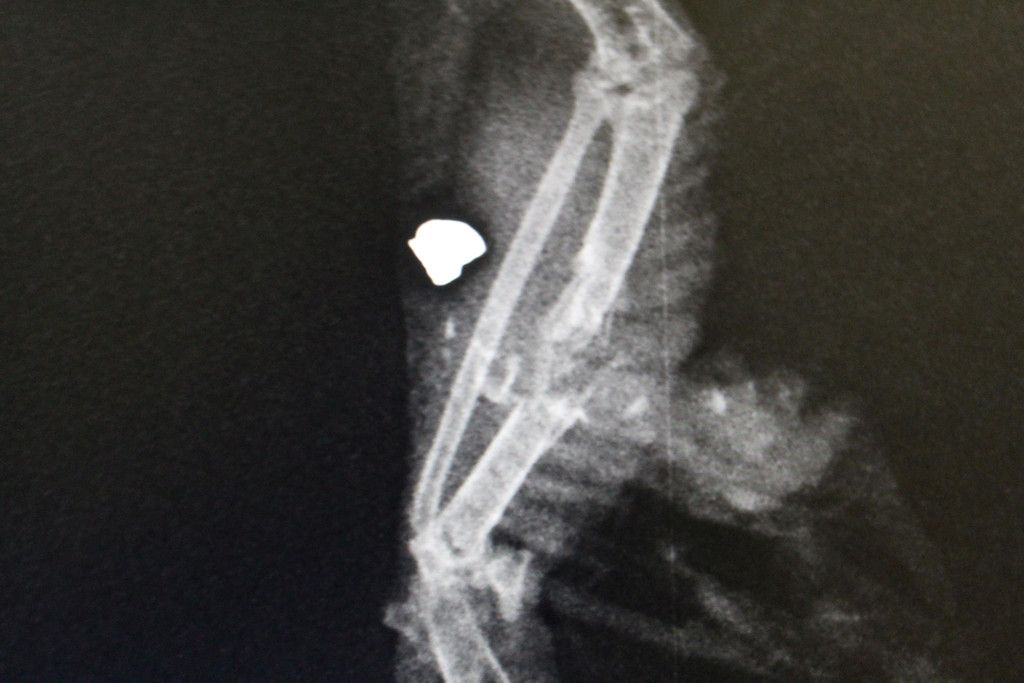

Angeschossene Taube landet beim WTV: Projektil im Flügel